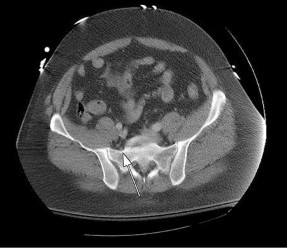

CLINICAL SITUATION FOR QUESTIONS 37 THROUGH 39

A 22-year-old woman has had right hip pain for 12 months. Her symptoms have not improved with nonsurgical treatment involving physical therapy and intra-articular injections.

A

B

35

C D E

The plain radiographs and MR image shown in Figures 37a through 37c indicate which condition?

- Cam-type femoroacetabular impingement with an acetabular labral tear